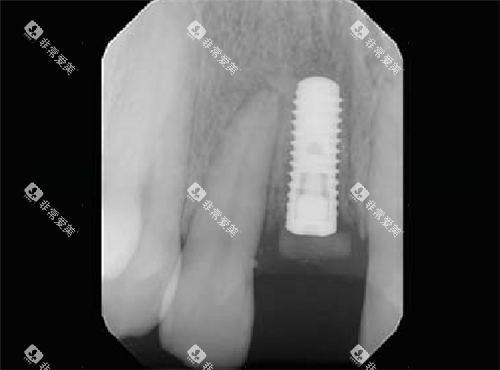

技术亮点:锥形设计模拟天然牙根,减少邻牙损伤

技术亮点:动态螺纹设计,稳定性提升60%